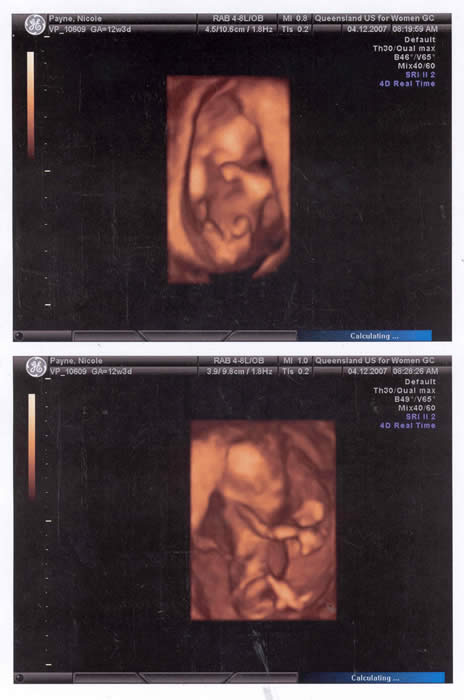

Our Baby at 13 weeks